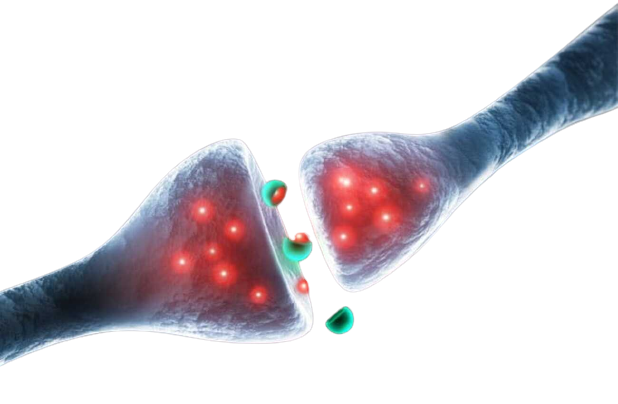

Silicon Valley, cuna de la innovación tecnológica, está experimentando una transformación silenciosa pero profunda: la integración de los psicodélicos en la cultura laboral. Lo que hace años se consideraba marginal o subversivo, hoy se ha convertido en una herramienta legítima para potenciar la creatividad, combatir el agotamiento y redefinir el bienestar en la meca tecnológica. De la marginalidad a la integración terapéutica La llamada integración psicodélica, guiada por terapeutas especializados, es ahora una práctica común entre ingenieros, emprendedores y ejecutivos del sector tecnológico.